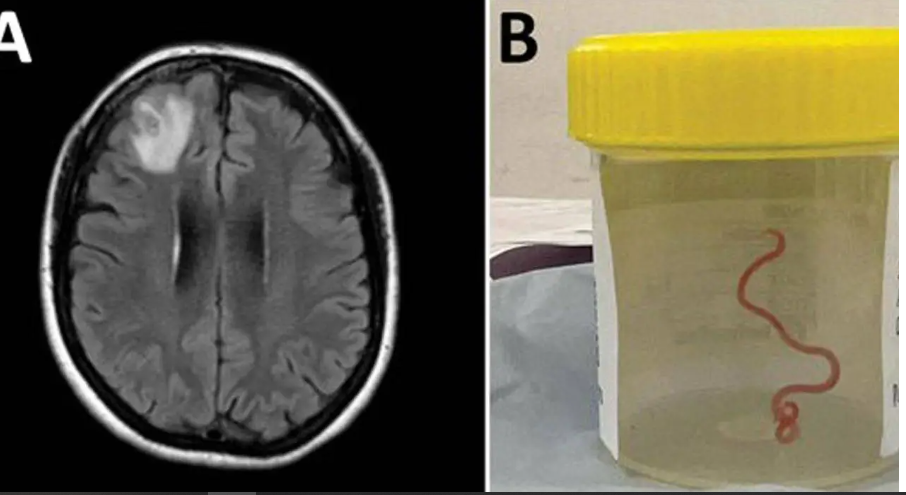

في واقعة تعد غريبة من نوعها أقيمت جراحة تعد نادرة لسيدة أسترالية تدعى هاري برييا باندي، تبلغ من العمر 64 عاماً وتعاني من وجود دودة طفيلية طويلة يبلغ طولها حوالي 8 سنتيمترات وقد خرجت من مخ المريضة وهي تتلوى بين ملقاط الجراحين وذلك بعد الانتهاء من العملية، خاصةً أن السيدة لم تلتقِ من قبل بهذا النوع من الديدان وذلك سوى في نطاق القيام ببعض أعمال البستان في حديقتها.

وأكد خبير في علم الطفيليات أنها المرة الأولى التي ينتقل الطفيل إلى المخ، وذلك سواء لدى الإنسان أو بعض الفصيلات الثديية وذلك بشكل عام.

وأكدت الفحوصات أن الدودة المُكتشفة تنتمي لفصيلة «اوفيداسكاريس روبيرتسي» والتي تعد الشائعة بين الثعابين.

وأشار الباحثون إلى أن السيدة كانت تعيش في منطقة تطل على بحيرة يسكنها أحد أنواع الثعابين ومن المرجح أن تكون السيدة قد أُصيبت بالدودة المستديرة وذلك عقب لمسها لبعض الخضراوات الورقية المحلية المصابة بالطفيل وذلك عبر فضلات الثعابين.